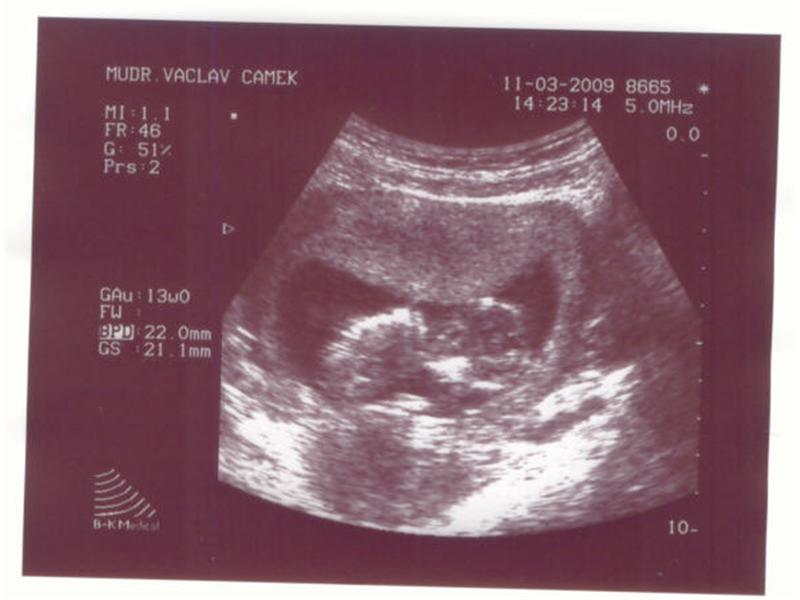

když jsem byl ještě u maminky v bříšku

Zdroj: archiv redakce